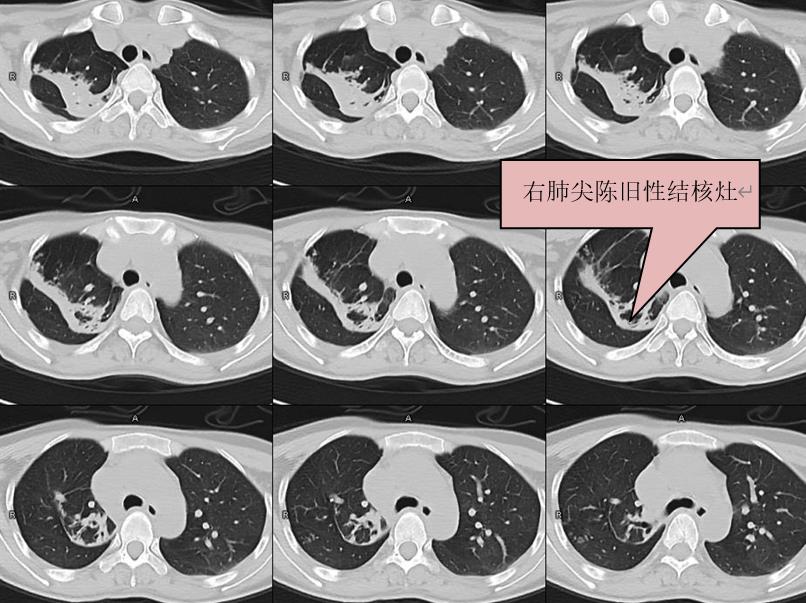

在了解病情后,专家决定应用中心西门子目前最先进的Force双源CT对患者进行颈部增强检查,同时扫描包括了上胸段一部分,检查后发现林女士肺内有一部分陈旧性结核灶(见下图),这也是为什么她会被外院医生诊断为 “结核”。